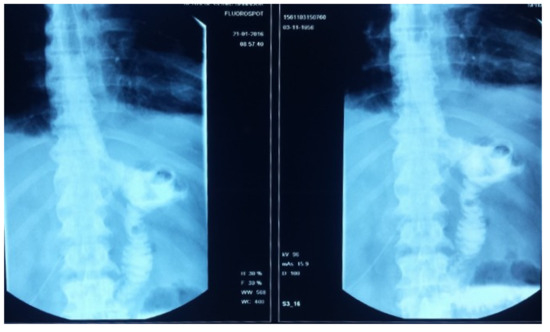

After the gastrectomy, the patient underwent X-ray radiography (Figure 4). Four weeks later, the patient developed a marked inflammatory syndrome (erythrocyte sedimentation rate (ESR) 100 mm, White Cell Count (WCC) 20,000, C-Reactive Protein test (CRP) 30, raised procalcitonin test, and pyrexia). The clinical examination revealed a diastolic aortic murmur with collapsing pulses. The transthoracic ECHO detected multiple aortic leaflet vegetations with severe regurgitation (grade IV). Blood cultures identified Staphylococcus saprophytic. As there was no existence of dental infections, malnutrition, or preexistent aortic lesions, due to the cancer and preexistent co-morbidities, the patient developed a paraneoplastic immune depression that resulted in the Staphylococcus saprophytic infection.

Figure 4. Radiological image after total gastrectomy and gastrojejunoanastomosis.